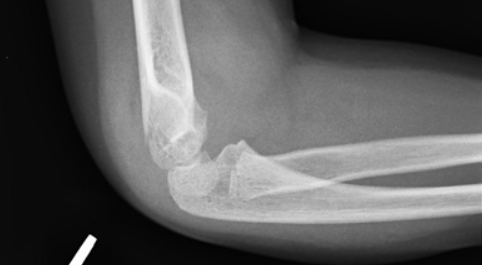

A 13 year old boy present to your ED on a Saturday evening. He was at a birthday party and fell from a table onto an outstretched hand with his left elbow in extension. He is refusing to move his elbow due to pain and you decide to get an x-ray (shown bellow).

If we apply what we have learned to the following example:

- The boy has normal ossifications centers for his age

- He has a posterior fat pad present

- He has a normal radiocapitellar line but an abnormal anterior humeral line

- His neuromuscular exam was normal and he has no evidence of compartment syndrome

This 14 year old boy was therefore treated as a displaced supracondylar fracture